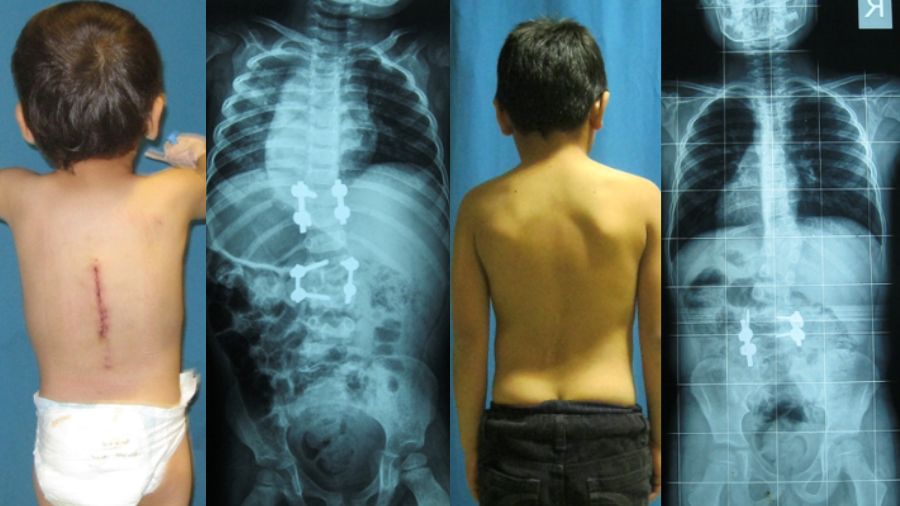

Congenital scoliosis generally presents alongside other syndromes, such as VATER Syndrome (Vertebra, Anus, Trachea, Esophagus, and Renal Syndrome), but in many cases, there is no associated chromosomal or genetic problem. This was the case with two really interesting patients I treated, who were actually siblings. The brothers shared a very similar congenital deformity and came to me when the youngest was two years old and the eldest was six. We very seldom see cases like this – I haven’t found it before in any literature – and we couldn’t find any genetic disorder linking the siblings.

The boys both had contralateral hemivertebra, but with differing degrees of severity, and I followed different treatment strategies for the two patients. The younger boy had a hemivertebra in the middle of the lumbar spine, at L-2, and another in the lower thoracic spine around T-10. The older patient had similar deformity pattern with contralateral lumbar and thoracic hemivertebrae. These patients live in a rural area, otherwise it is likely that the spinal deformity would have been picked up at an earlier stage. Congenital scoliosis can cause a severe deformity of the spine, leading to problems such as respiratory insufficiency and neural impairment.

In the case of these brothers, the older brother’s deformity was relatively well controlled, and upper curvature was quite mild, whereas both curves of younger boy were high magnitude. For the younger sibling I was able to excise both hemivertebrae. With localized problems like this, say two or maximum three segments, we are often able to perform a short segment fusion and excision. If we were to wait for excision of the hemivertebra for a long time, we may end up with a reciprocal change in spinal column and necessity of long fusion construct. By taking action earlier we can arrive at a solution with very limited surgeries and without jeopardizing their maturation and growth.

Surgical revision may be necessary as patient reaches adolescence

At the follow-up scans, we found that the younger sibling had recovered very well, and his spine was well aligned. For the older brother, I only removed one hemivertebra, and decided to follow the progress of the other. At the follow-up scans he is not so well aligned - in fact the upper thoracic vertebra is totally unbalanced, creating a deterioration of the curvature in the thoracic part. This is clearly evident in the radiographs but in terms of clinical appearance, he looks fine as you can see in the picture.